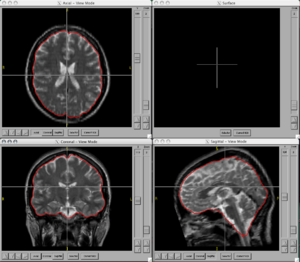

BRAINSCut is a software package for segmentation of structures using artificial neural networks. Currently this tool supports the segmentation of the following structures: brain, caudate, putamen, thalamus, hippocampus, anterior cerebellum, interior posterior cerebellum, superior posterior cerebellum, corpus medullary. Future regions will include the globus pallidus, amygdala, and nucleus accumbens. The command line uses the Slicer3 execution model framework.

Figures

- BRAINSCut